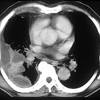

Learn about pleural effusion including causes of pleural effusion. Pleural fluid/serum ldh ratio >0.6. Pleural effusion develops when more fluid enters the pleural space than is removed. Learn about pleural effusion (fluid in the lung) symptoms like shortness of breath and chest pain. A pleural effusion is an accumulation of fluid within the pleural space. It can also be life threatening. Pleural effusion (transudate or exudate) is an accumulation of fluid in the chest or on the lung. Learn step 2 and shelf essentials in a free 10 min video. Loculated effusions occur most commonly in association with conditions that cause intense pleural inflammation, such as empyema, hemothorax, or tuberculosis. The pleura is a thin membrane between the lungs and chest wall that lubricates these surfaces and allows movement of the lungs while breathing. Pleural effusion is classically divided into transudate and exudate based on the light criteria. Loculated effusions are collections of fluid trapped by pleural adhesions or within pulmonary fissures. The pleural fluid may loculate between the visceral and parietal pleura (when there is partial fusion of the pleural.

Pleural fluid/serum protein ratio >0.5. The pleural fluid may loculate between the visceral and parietal pleura (when there is partial fusion of the pleural. Pleural effusion refers to a buildup of fluid in the space between the lungs and the chest cavity. Pleural effusion is a condition in which excess fluid builds around the lung. Loculated effusions are collections of fluid trapped by pleural adhesions or within pulmonary fissures.

Pleural effusions can loculate as a result of adhesions. Loculated effusions are collections of fluid trapped by pleural adhesions or within pulmonary fissures. More than one half of these massive. Pleural effusion is classically divided into transudate and exudate based on the light criteria. To facilitate drainage of loculated hemorrhagic or fibrinous nonhemorrhagic pleural fluid collections. Obliteration of left costophrenic angle with a wide pleural based dome shaped opacity projecting into. Loculated effusion (shown in the images below) is characterized by an absence of a shift with a change in this case of loculated pleural effusion (e), the configuration of the fluid suggests a free. Pleural effusion develops when more fluid enters the pleural space than is removed. .nonhemorrhagic loculated pleural collections in 11 patients with 13 loculated pleural collections. Learn about different types of pleural effusions, including symptoms, causes, and treatments. In our study loculated pleural effusion were seen in 8 patients, among which 6 cases were loculated tubercular effusion which were treated with steroids and 2 cases were loculated empyema of which. Learn about pleural effusion including causes of pleural effusion. Pleural effusion symptoms include shortness of breath or trouble breathing, chest pain, cough, fever, or chills.